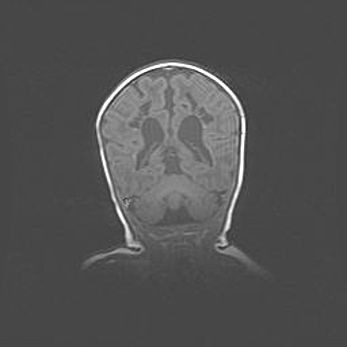

Открытая гидроцефалия.

Возраст: 9 месяцев 12 дней

Вес: 6800 г

Пол: мужской

Окружность головы: 41,5 см

Срок гестации: 28 недель

Гидроцефалия головного мозга у новорожденных имеет характерный признак: опережающий рост окружности головы приводит к визуально хорошо определяемой гидроцефальной форме сильно увеличенного в объёме черепа. Детские неврологи определяют следующие симптомы гидроцефалии у грудничков: выбухающий напряжённый родничок, частое запрокидывание головы, смещение глазных яблок к низу.